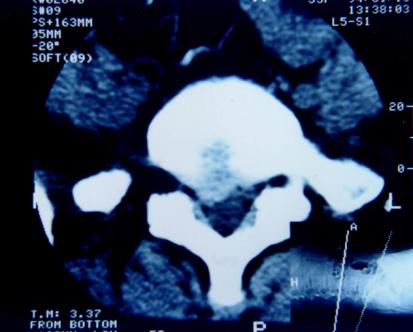

CT检查:具有确诊价值。将人体的脊柱的通过CT扫描仪,各个平面扫下来,总能看到你想要看到的层面,但CT只能看到密度较高的东西,如骨头、骨质,而对于神经等相对“软”的东西,敏感性不佳。